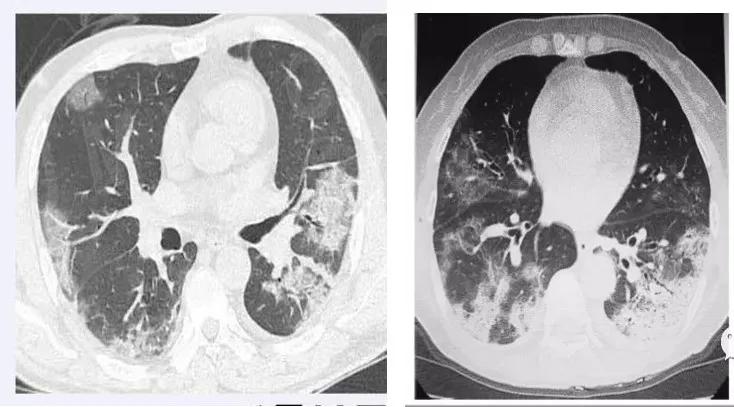

对成人来说,新冠病毒感染后淋巴细胞减少比较明显,但在儿科表现不那么明显,因此儿童新冠病毒感染通常查血常规没有特异性。儿童新冠病毒感染,相对特异性的检查是肺部CT。毛玻璃样的影子从周边向中间慢慢地播散的特点是比较明显的。湖北地区曾经用CT进行临床诊断,当时对控制传染源起了很大作用。新冠病毒感染最后的确诊,还需要病原学检查,如核酸检查、抗体检查等。